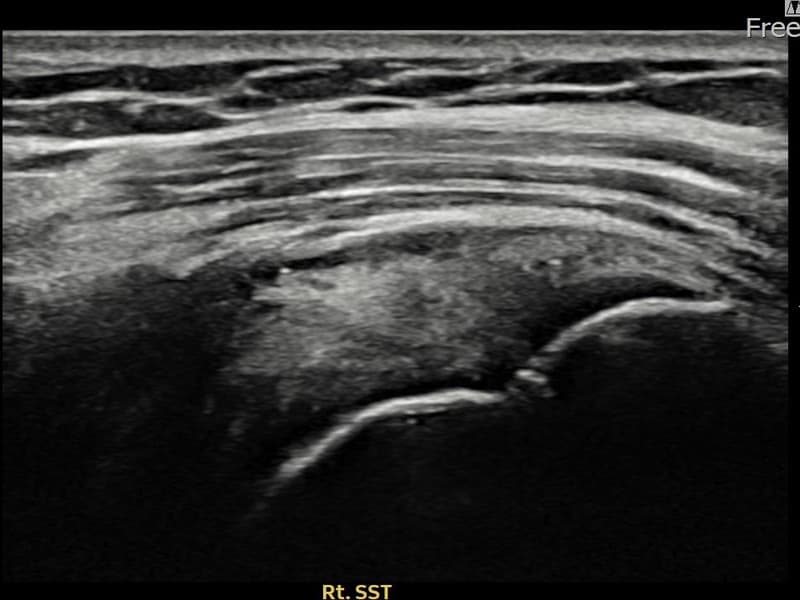

术后

术前超声确认右侧 冈上肌腱 滑囊面侧部分撕裂,右侧冈上肌腱回声不连续伴肌腱缺损(8mm × 4mm (肌腱厚度约35%缺损))。术后超声显示撕裂部位充满再生组织,肌腱连续性恢复,回声模式正常化。